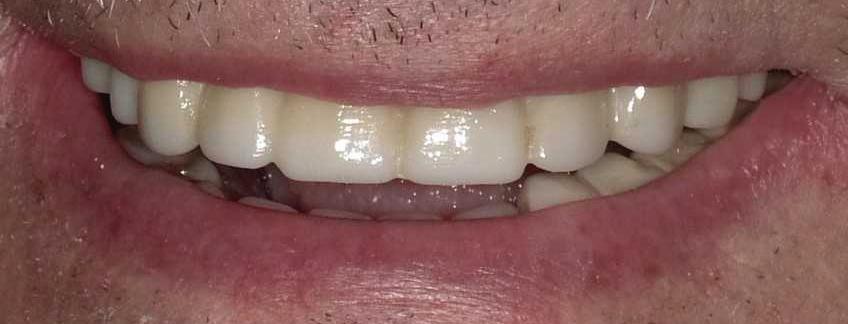

Can just four implants replace all of the teeth on the top or the bottom of your mouth? Thanks to advances in dental implant technology, that answer is a resounding yes.

Tooth loss is extremely common among adults, especially as we age. Rather than living with the discomfort and hassles of dentures, many people are opting for what is called “all-onfour” dental implant restoration.

An implant is a small titanium

screw that fits inside your jawbone and replaces the root-part of a missing tooth. Minor surgery is required to insert the implants. Once the implant is in place, a crown is attached to give you a highly realistic-looking and functional prosthetic tooth.

You do not need a dental implant for each and every one of your missing teeth. All you need is four precisely placed implants on the top of your mouth, and four on the bottom, to restore your full smile. That’s the beauty of the all-on-four. And because the implant is made of titanium, it has the unique ability to fuse to living bone and function as part of it. So eventually, the dental implant becomes part of the jawbone and serves as a strong, longlasting foundation for your new teeth.

Besides ensuring that your implants are permanently fixed in place, this bone fusion has another important benefit: it prevents future bone loss in the jaw. This helps to maintain a more youthful facial structure – and better

Please see “All-On-Four,” page 63